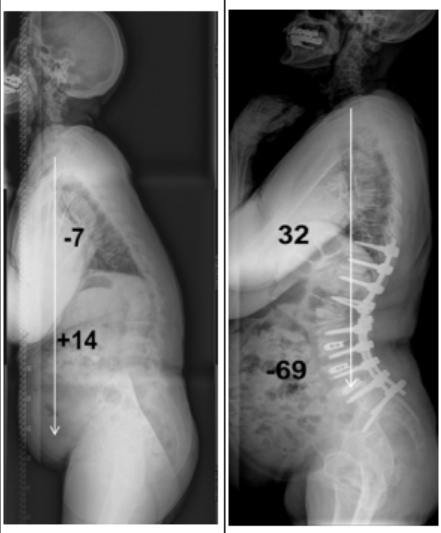

- ▲ 60대 여성의 척추후만증 수술 전(왼쪽), 후 ⓒ경희의료원

이정희 교수는 “앞으로 숙여지는 각도 보다 환자가 느끼는 증상이 중요하다”며 “척추 후만증 수술은 환자의 골반지수에 따른 교정각도가 다르기 때문에 반드시 전문의와의 상담으로 수술 여부를 결정해야 한다”라고 밝혔다. 수술은 척추 변형술로 진행하며 환자의 증상과 검사 결과, 수술 전 환자의 생활능력 등을 고려해 이뤄진다.